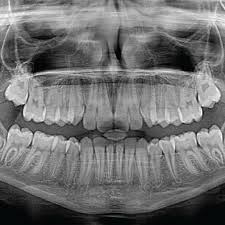

Dental X Ray Opg In 2020 Dental Facial Bones X Ray